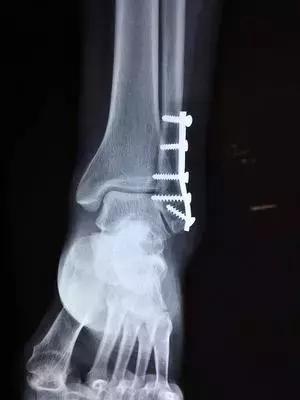

2.固定

骨折复位后,因不稳定,容易发生再移位,因此要采用不同的方法将其固定在满意的位置,使其逐渐愈合。常用的固定方法有:小夹板、石膏绷带、外固定支架、牵引制动固定等,这些固定方法称外固定。如果通过手术切开用钢板、钢针、髓内针、螺丝钉等固定,则称内固定。

三、骨折的X线检查

凡疑为骨折者应常规进行X线拍片检查,可以显示临床上难以发现的不完全性骨折、深部的骨折、关节内骨折和小的撕脱性骨折等。即使临床上已表现为明显骨折者,X线拍片检查也是必要的,可以帮助了解骨折的类型和骨折端移位情况,对于骨折的治疗具有重要指导意义。

骨折的X线检查一般应拍摄包括邻近一个关节在内的正、侧位片,必要时应拍摄特殊位置的X线片。如掌骨和跖骨拍正位及斜位片,跟骨拍侧位和轴心位,腕舟状骨拍正位和斜位。有时不易确定损伤情况时,尚需拍对侧肢体相应部位的X线片,以便进行对比。值得注意的是,有些轻微的裂缝骨折,急诊拍片未见明显骨折线。如临床症状较明显者,应于伤后2周拍片复查。此时,骨折端的吸收常可出现骨折线,如腕舟状骨骨折。